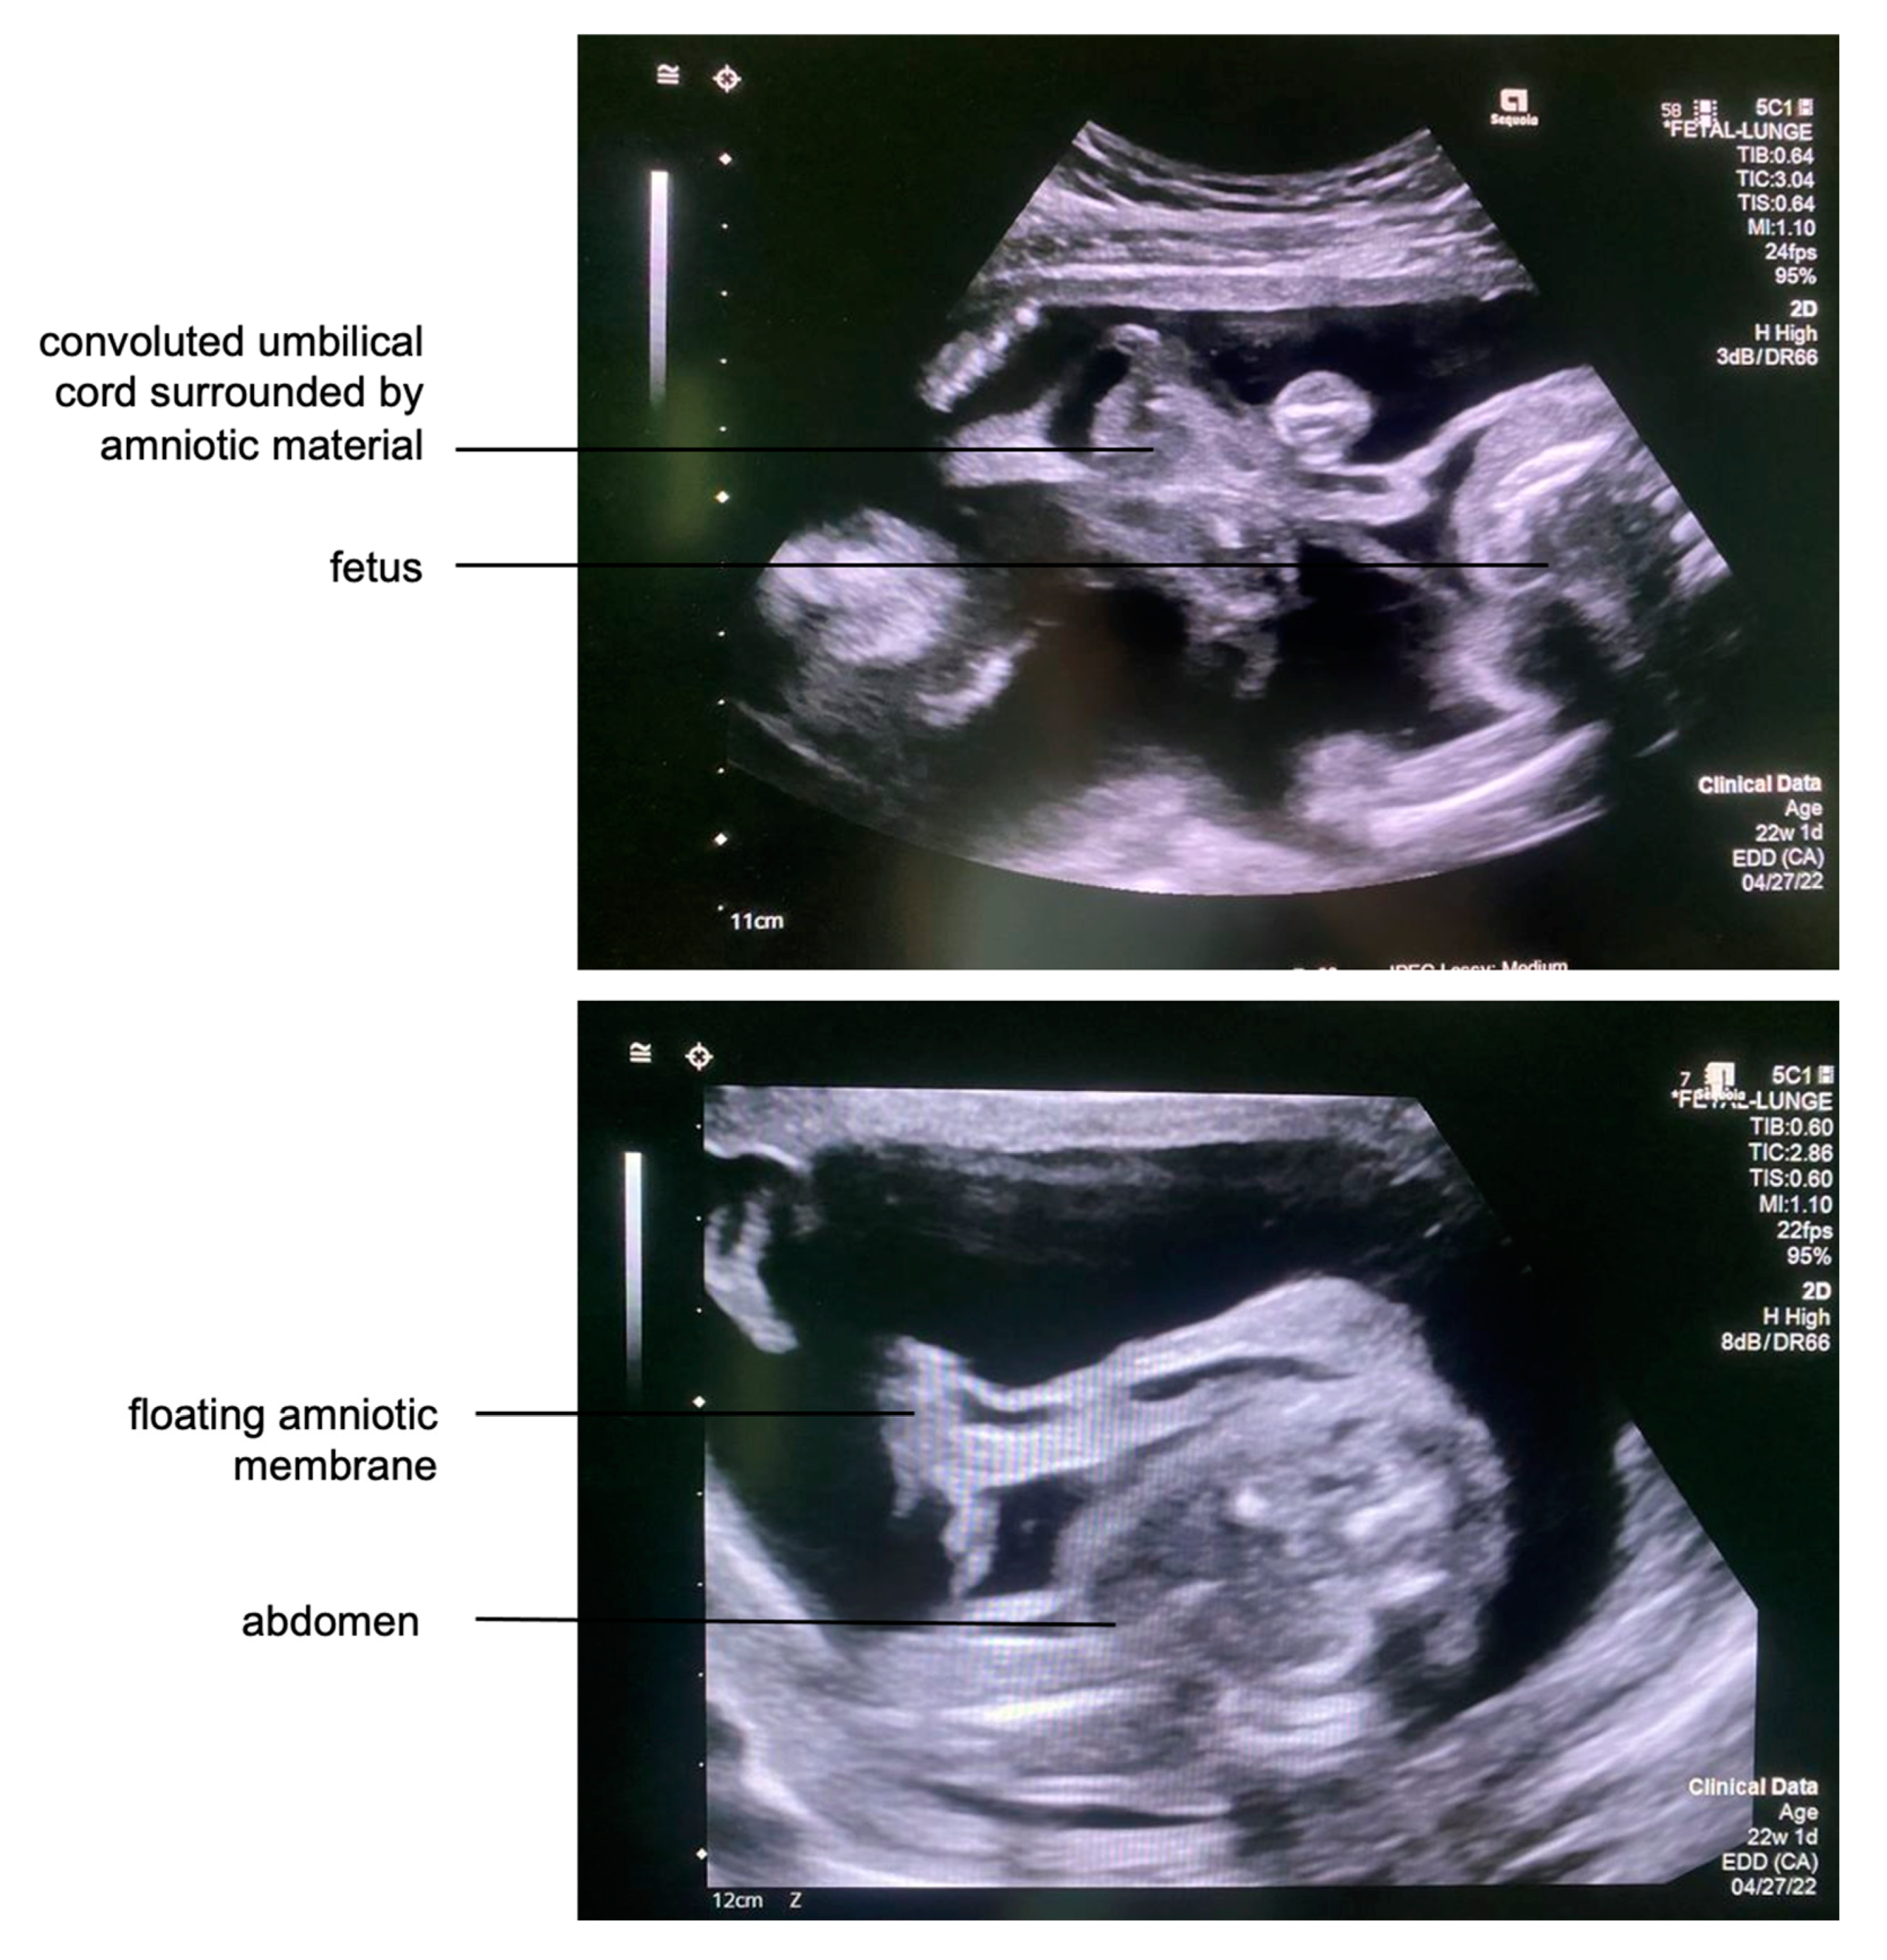

Several loops of the umbilical cord were entangled in amniotic tissue and parts of the abrupted placenta. Due to localized entrapment of umbilical cord slings and increased umbilical venous blood flow velocities, a constriction of the umbilical cord was suspected. Strangulation of the right calf was also noted, with associated edema extending down to the foot (Figure 2). A Doppler ultrasound assessment of the right leg indicated that the fetus might benefit from amniotic band removal as it showed decreased venous blood flow distal to the constriction, heralding the risk of limb loss without prompt intervention. Furthermore, the left leg protruded through the abrupted placental segment.

Figure 2. Top: The fetal right calf was strangulated by an amniotic band with distal limb edema due to the constriction. Bottom: The right foot became severely enlarged from the development of edema.